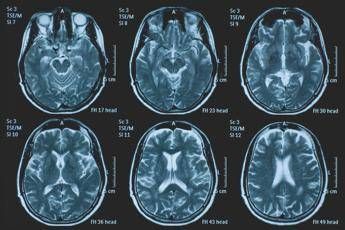

(Adnkronos) - La Commissione europea (Ce) ha autorizzato la commercializzazione condizionata di tovorafenib come monoterapia per il trattamento dei pazienti di età pari o superiore a 6 mesi con glioma pediatrico di basso grado che presentano una fusione o un riarrangiamento del gene Braf o una mutazione Braf-V600, in progressione di malattia dopo una o più terapie sistemiche precedenti. Lo annuncia Ipsen, in una nota, precisando che si tratta della “prima terapia mirata” per questa patologia e che la decisione della Ce si riferisce ai 27 Stati membri della Ue, oltre a Islanda, Liechtenstein e Norvegia. Ogni anno in Ue vengono diagnosticati più di 800 nuovi casi di glioma pediatrico di basso grado (pLgg) con alterazione di Braf. Questo tumore cerebrale, nonostante sia classificato di basso grado (a lenta progressione), comporta un carico significativo e permanente che accompagna la persona per tutta la vita, causando spesso importanti compromissioni fisiche e neurologiche, tra cui perdita della vista, difficoltà di linguaggio e disfunzioni motorie, che possono incidere in modo significativo sull’istruzione, l’autonomia e la qualità di vita a lungo termine del bambino. Finora, molti bambini con pLgg hanno dovuto sottoporsi a interventi chirurgici invasivi, a più cicli di chemioterapia e a radioterapia, con conseguenti complicazioni della salute. “Per i piccoli che ricevono la diagnosi di glioma di basso grado, il percorso è spesso lungo e difficile, con opzioni terapeutiche limitate - afferma Sandra Silvestri, Executive Vice President and Chief Medical Officer, Ipsen - Questa approvazione rappresenta un passo avanti significativo per questi bambini e per le loro famiglie, rafforzando al contempo il nostro impegno a rispondere a elevati bisogni clinici non soddisfatti. Ora il nostro obiettivo è garantire che i bambini eleggibili in tutta Europa possano accedere a questa terapia il più rapidamente possibile”. L’approvazione della Ce si basa sui dati dello studio di fase 2 Firefly-1 che ha valutato tovorafenib in 137 bambini e giovani adulti con pLgg recidivato o refrattario con alterazioni di Braf che avevano ricevuto almeno una precedente terapia sistemica. Nel dettaglio, lo studio ha dimostrato una risposta tumorale clinicamente significativa con un tasso di risposta globale del 71% secondo i criteri Rano-Hgg (ResponseAssessment in Neuro-Oncology criteria for High-Grade Gliomas) e del 53% secondo i criteri Raono-Lgg (Response Assessment in Paediatric Neuro-Oncology for Low-Grade Glioma), con un tasso di beneficio clinico del 77% secondo i criteri Rano-Hgg e del 58% secondo i criteri Rapno-Lgg. Le risposte - riferisce la nota - sono state rapide e durature: sulla base dei criteri Rapno-Lgg, tra coloro che hanno risposto, il tempo mediano alla risposta è stato di 5,4 mesi con una durata mediana della risposta di 18 mesi. Sul profilo di sicurezza, tovorafenib è stato generalmente ben tollerato, con eventi avversi legati al trattamento (Traes) prevalentemente di grado 1 o 2 e un tasso di interruzione basso (9,5% dei pazienti ha interrotto il trattamento a causa di eventi ritenuti dallo sperimentatore correlati a tovorafenib). I Traes più comuni comprendevano variazione del colore dei capelli, creatinfosfochinasi ematica alta, fatigue, anemia, vomito, ipofosfatemia, cefalea, eruzione cutanea maculopapulare, febbre, ritardo della crescita, secchezza cutanea. Il regime posologico semplice, con la somministrazione orale una volta alla settimana, con o senza cibo, in formulazione liquida o in compresse, ha ridotto al minimo i disagi nella routine quotidiana. Le famiglie con piccoli colpiti dal glioma di basso grado “spesso devono affrontare anni di incertezza, difficili decisioni terapeutiche e il timore delle conseguenze a lungo termine”, evidenzia François Doz, professore di Pediatria alla Paris Descartes University, vicedirettore di Clinical Research, Innovation and Teaching al Siredo Oncology Centre of the Curie Institute (Assistenza, innovazione e ricerca nel campo dei tumori dell'infanzia, dell'adolescenza e dei giovani adulti) e direttore didattico dell’Hospital Ensemble of the Institut Curie. Il regolamento dell'Ue sulla valutazione delle tecnologie sanitarie (Health Technology Assessment – Hta -Regulation), la cui attuazione è iniziata progressivamente a partire da gennaio 2025 - conclude la nota - ha introdotto un nuovo processo di valutazione clinica congiunta (Joint Clinical Assessment - Jca) volta a semplificare e armonizzare la revisione comparativa delle evidenze cliniche negli Stati membri dell'UE. Tovorafenib è il primo farmaco a essere sottoposto a una valutazione Jca.